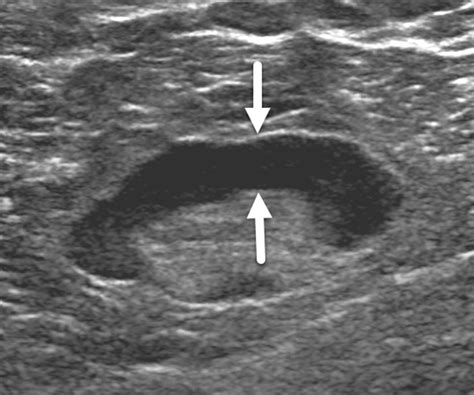

• Size and Shape: Normal nodes are typically oval, whereas malignant nodes may appear more rounded or spherical.

• Internal Architecture: Healthy nodes have a clear, bright central area called the “fatty hilum.” The absence of this hilum can be a warning sign.

• Border Definition: Clear, regular borders are generally reassuring, while irregular or “matted” borders may warrant biopsy.